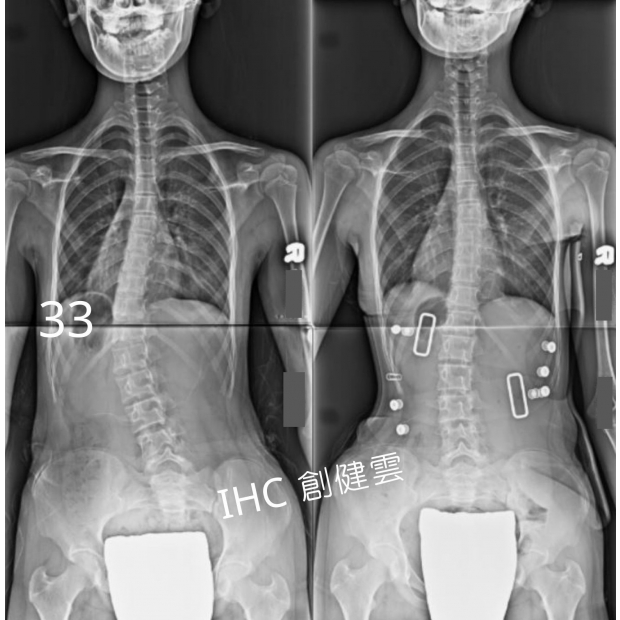

14歲C型脊椎側彎女孩

胸腰彎33度